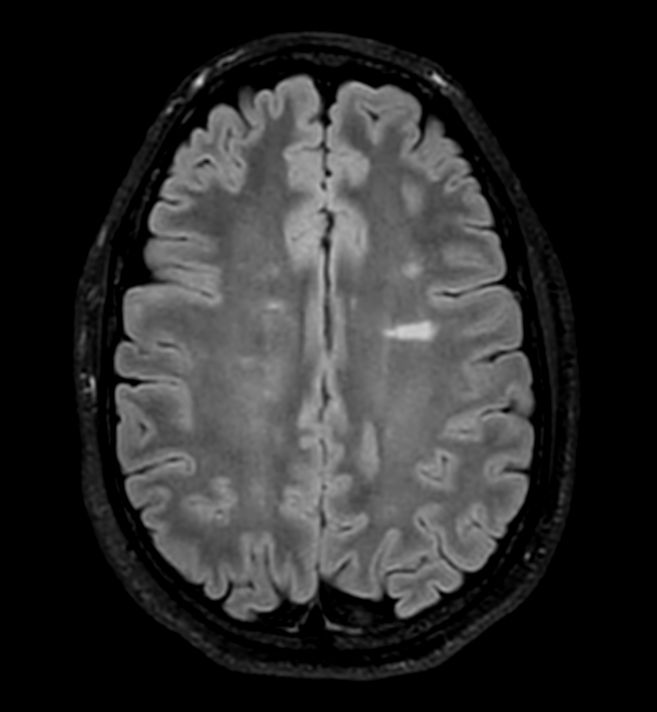

Axial 3D VIEW - T2w FLAIR

-